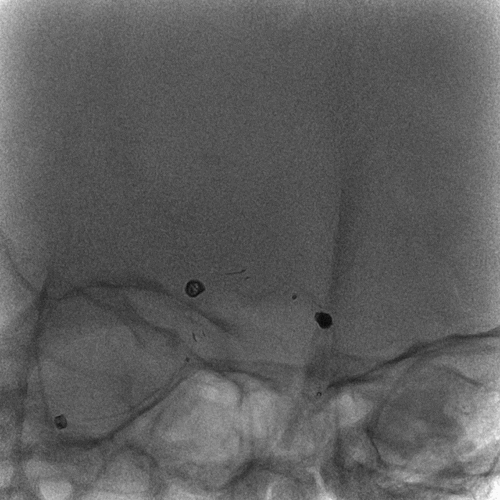

左侧颈内动脉造影

右侧颈内动脉造影

双侧椎动脉造影

压颈造影及压颈3D